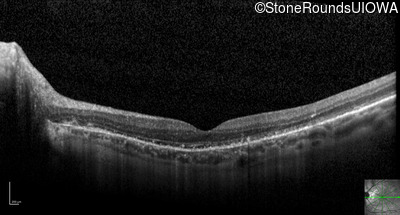

Optical Coherence Tomography - Right - 20/25 +1

Exemplar / OCT Stack